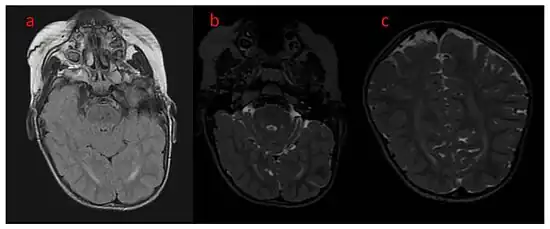

a–c) Brain MRI, T2 FLAIR , and coronal show unfinished myelinisation of white matter surrounding occipital horns.

While initial diagnosis is based mostly on clinical suspicion, definitive diagnosis requires confirmation by genetic testing. The first presentation of epileptic seizures within the first few months of life would suggest a possible diagnosis of CDD. Initial clinical testing for differential diagnosis may include MRI and CSF testing for structural or infectious etiologies; however, CDKL5 is now widely included in DNA sequence-based molecular diagnostic gene panels or infantile epilepsy for more rapid and precise diagnosis. Note: many adolescents and young adults may have CDD but were never tested since such tests were not available when they were infants. Therefore, epilepsy panels for CDD and other genes should be considered in such individuals.[8]